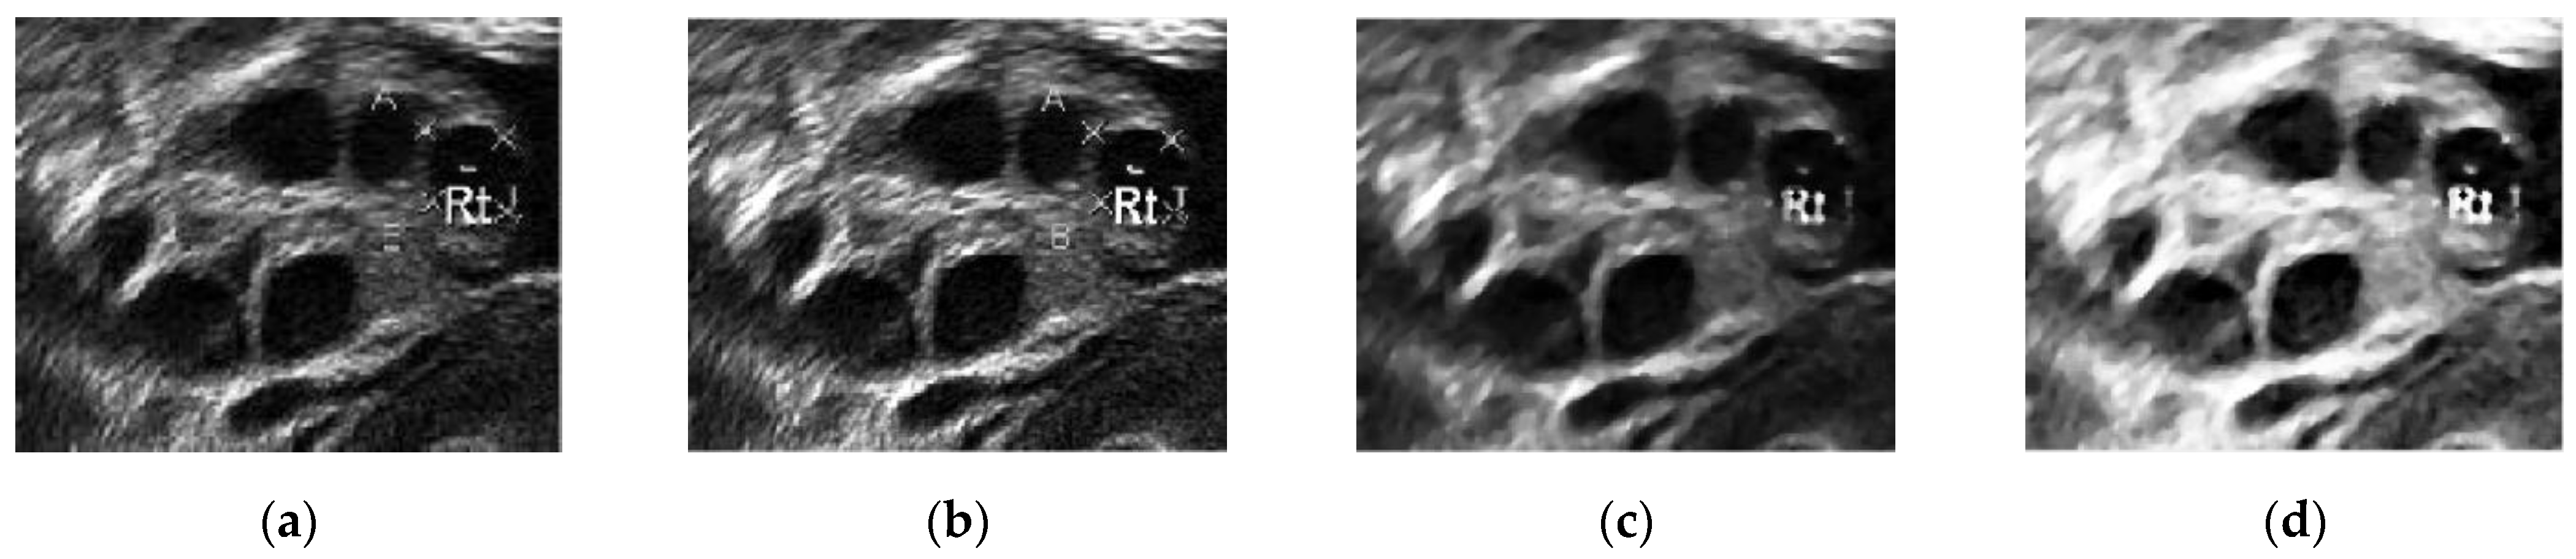

Figure 10 presents the images in the pre-processing step: intensity transformation, median filter, and histogram equalization. Figure 10a shows the ultrasound image before any pre-processing steps were taken. Speckle noise disturbances were found throughout the image. As a result, the image was of poor quality, with some parts of the wall lining seeming to portray the existence of follicles.

Figure 10.

(a) Original ultrasound image, (b) ultrasound image after contrast enhancement, (c) ultrasound image with median filter, and (d) ultrasound image after histogram equalization.

Contrast enhancement adjusts the brightness and darkness of the ultrasound image to improve the image [53] and help reduce the speckle noise. In Figure 10b, the difference between the image pixels in the light and dark areas was improved by contrast enhancement. Furthermore, less speckle noise was observed the image. However, the leftover speckle noise residue, especially in the ovary wall lining, could still affect the segmentation process. Hence, Figure 10c shows the image after median filtering. The median filter smoothened the image and reduced the speckle noise disturbances while keeping the edge of the follicles’ boundaries. Figure 10d shows the image after histogram equalization, showing that equalization helped reduce speckle noise disturbances and visualize great separation between the dark and light areas of the image.